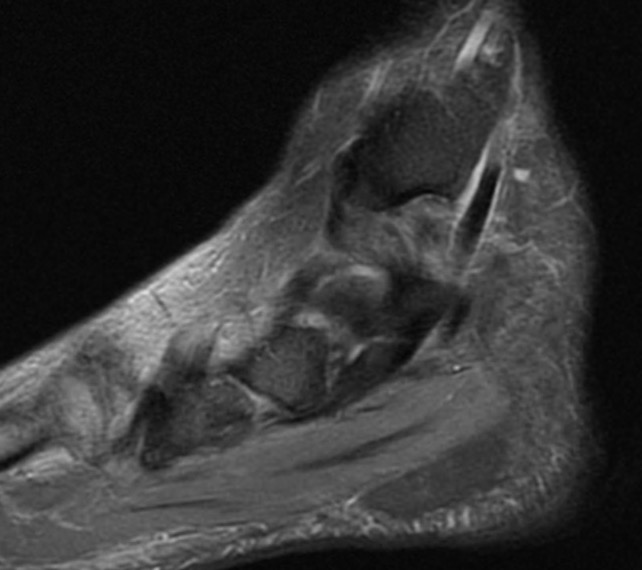

MRI

Tendonitis - fluid around tendon

Tendinopathy - tendon thickening

Tears

Tear tibialis posterior with 10 cm gap